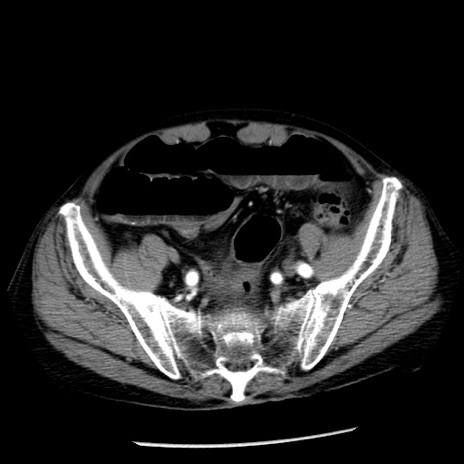

症例26(横断像)

【症例】80歳代男性

【主訴】嘔吐

【現病歴】昨晩2回嘔吐あり、今朝になっても嘔吐あり。来院。

【既往歴】胃潰瘍

【身体所見】意識清明、BT 37.6℃、BP 166/95mmHg、HR 100bpm、SpO2 97%、腹部:平坦・軟、腸蠕動音聴取良好、圧痛なし。

【データ】WBC 21900、CRP 1.46